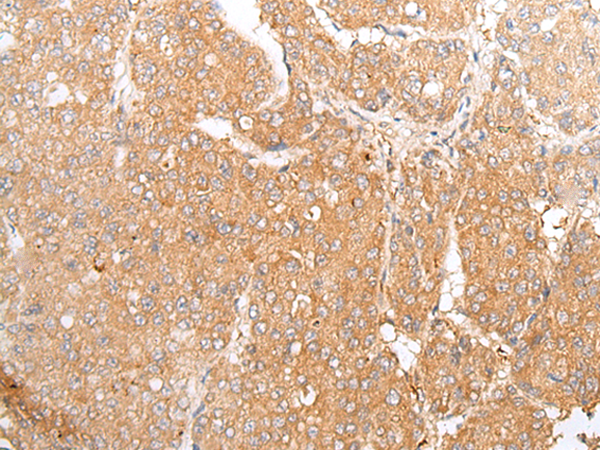

ELISA, IHC |

IHC positive control: |

Human liver cancer |

IHC Recommend dilution: |

25-100 |